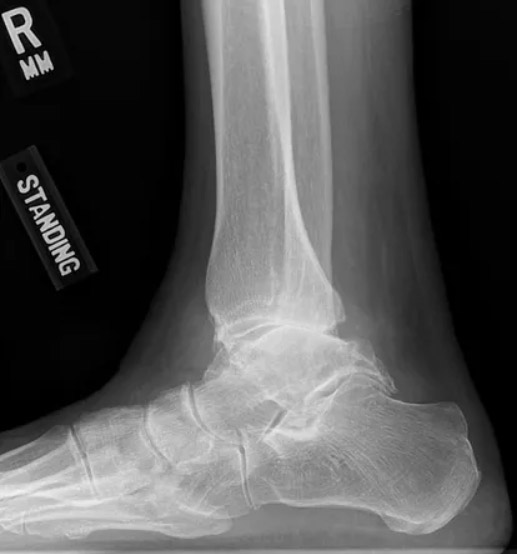

Arthritis After Ankle Fusion . Surgeons most commonly use ankle fusion to treat severe ankle arthritis. People who have severe ankle damage from arthritis or a past injury may be candidates for ankle fusion. Ankle fusion is a type of surgery to fuse the bones of your ankle into one piece. It’s also known as ankle arthrodesis. Candidates will usually have ankle pain that is so severe that it interferes with walking and daily activities. Ankle fusion surgery is a procedure in which bones in your ankle are fused into one piece to relieve pain. An ankle fusion procedure, also known as ankle arthrodesis, is a surgical intervention aimed at stabilizing and immobilizing the ankle joint. This can lead to an increased rate of arthritis in those other joints. Also known as ankle arthrodesis, the surgery is usually done to treat severe degenerative ankle arthritis. The surgery is usually done to treat arthritis in the ankle. If arthritis has worn away the cartilage that cushions and. If this happens, you’ll likely need a second ankle. Nonunion occurs after 10 to 11 percent of surgeries. Loss of motion in the ankle after a fusion causes the other joints in the foot to bear more stress than they did prior to the surgery.